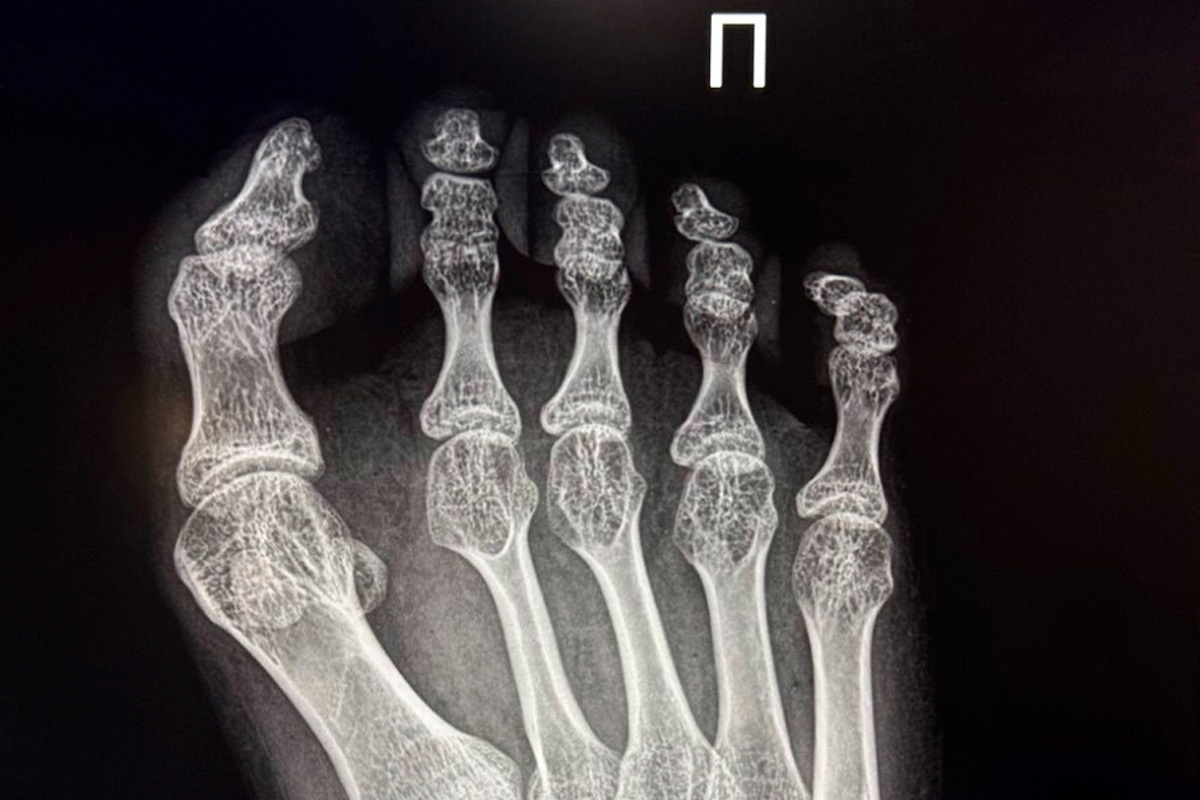

В Елецкой детской больнице Липецкой области была выполнена сложная операция для 17-летней девушки, которя страдает от детского церебрального паралича. Пациентка обратилась с жалобами на приобретенную деформацию первого пальца правой стопы 3 степени, которая причиняла ей значительные боли и затрудняла передвижение.

Заведующий травматологическим отделением, Махач Алиев, провел реконструктивное вмешательство, используя современные методики Шеде-Брандеса и Арина.